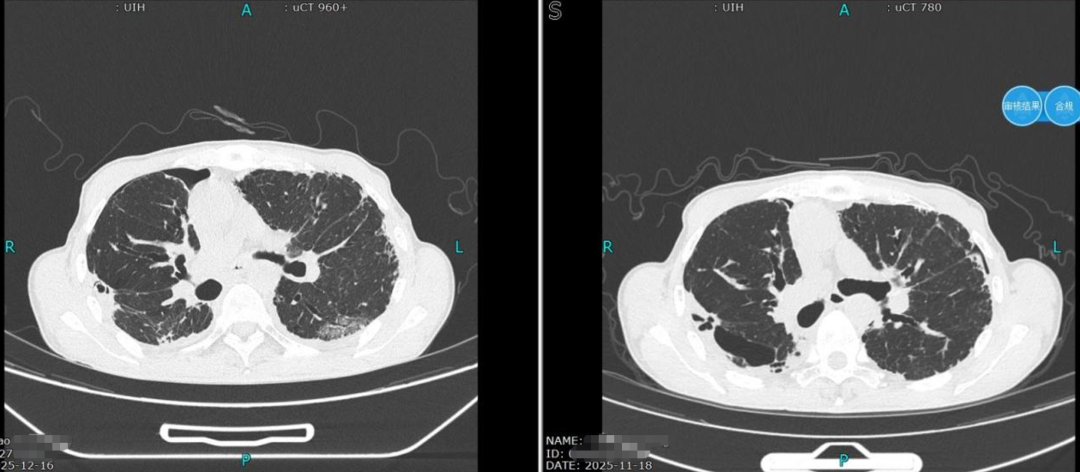

叶晋生结合检查报告分析诊断,刘大叔核心问题是气胸合并肺大疱,虽然肺压缩严重,但肺大泡集中在个别几个肺段,可通过微创胸腔镜手术精准处理,术后结合中医药恢复会更快。

术后第9天复查胸部CT,肺组织完全复张,顺利拔除引流管;